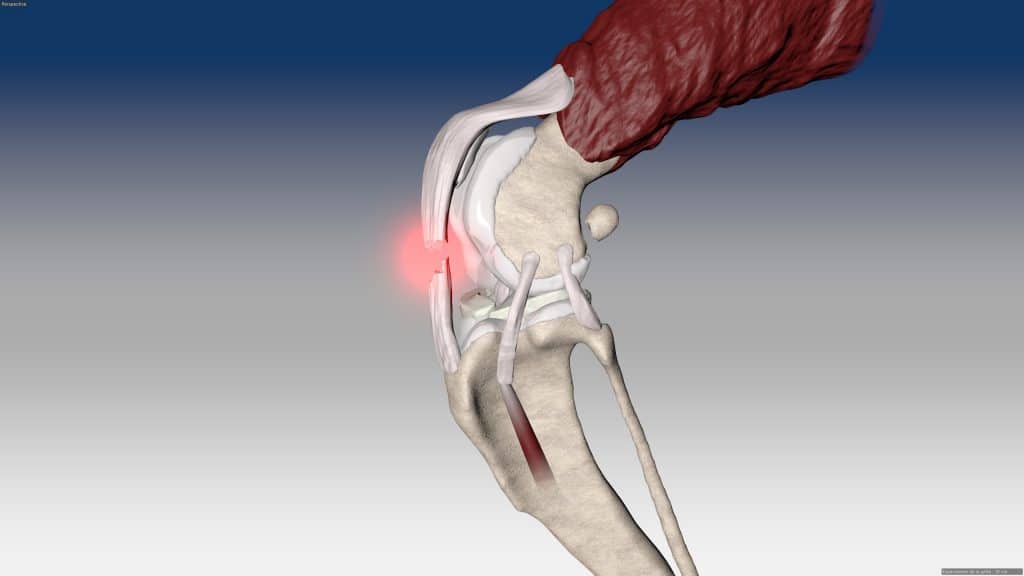

V případě zkřížených vazů umožňuje intraartikulární rekonstrukci v izometrických bodech připojení, čímž obnovuje biomechaniku kolene a všechny funkce natrženého vazu.

V případě více vazů kolene (kraniální, kaudální, kolaterální) je možné pomocí NOVALIG® anatomicky rekonstruovat každý vaz.